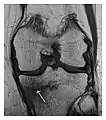

- a

- b

- c

Figure 1: A 56-year-old woman presenting with left knee pain after a fall. (a) Initial anteroposterior radiograph was considered normal, however, subtle cortical disruption of the anterior rim of the medial tibial plateau, medial to the tibial spine, is noted (arrow). (b) Coronal T1-weighted MRI confirms the cortical disruption (arrow) and shows extensive fracture through the proximal tibia. (c) Coronal proton density-weighted image with fat saturation shows extensive edema in the subchondral bone. Note also hypersignal adjacent to the medial collateral ligament corresponding to a grade I sprain (arrowheads).[1]